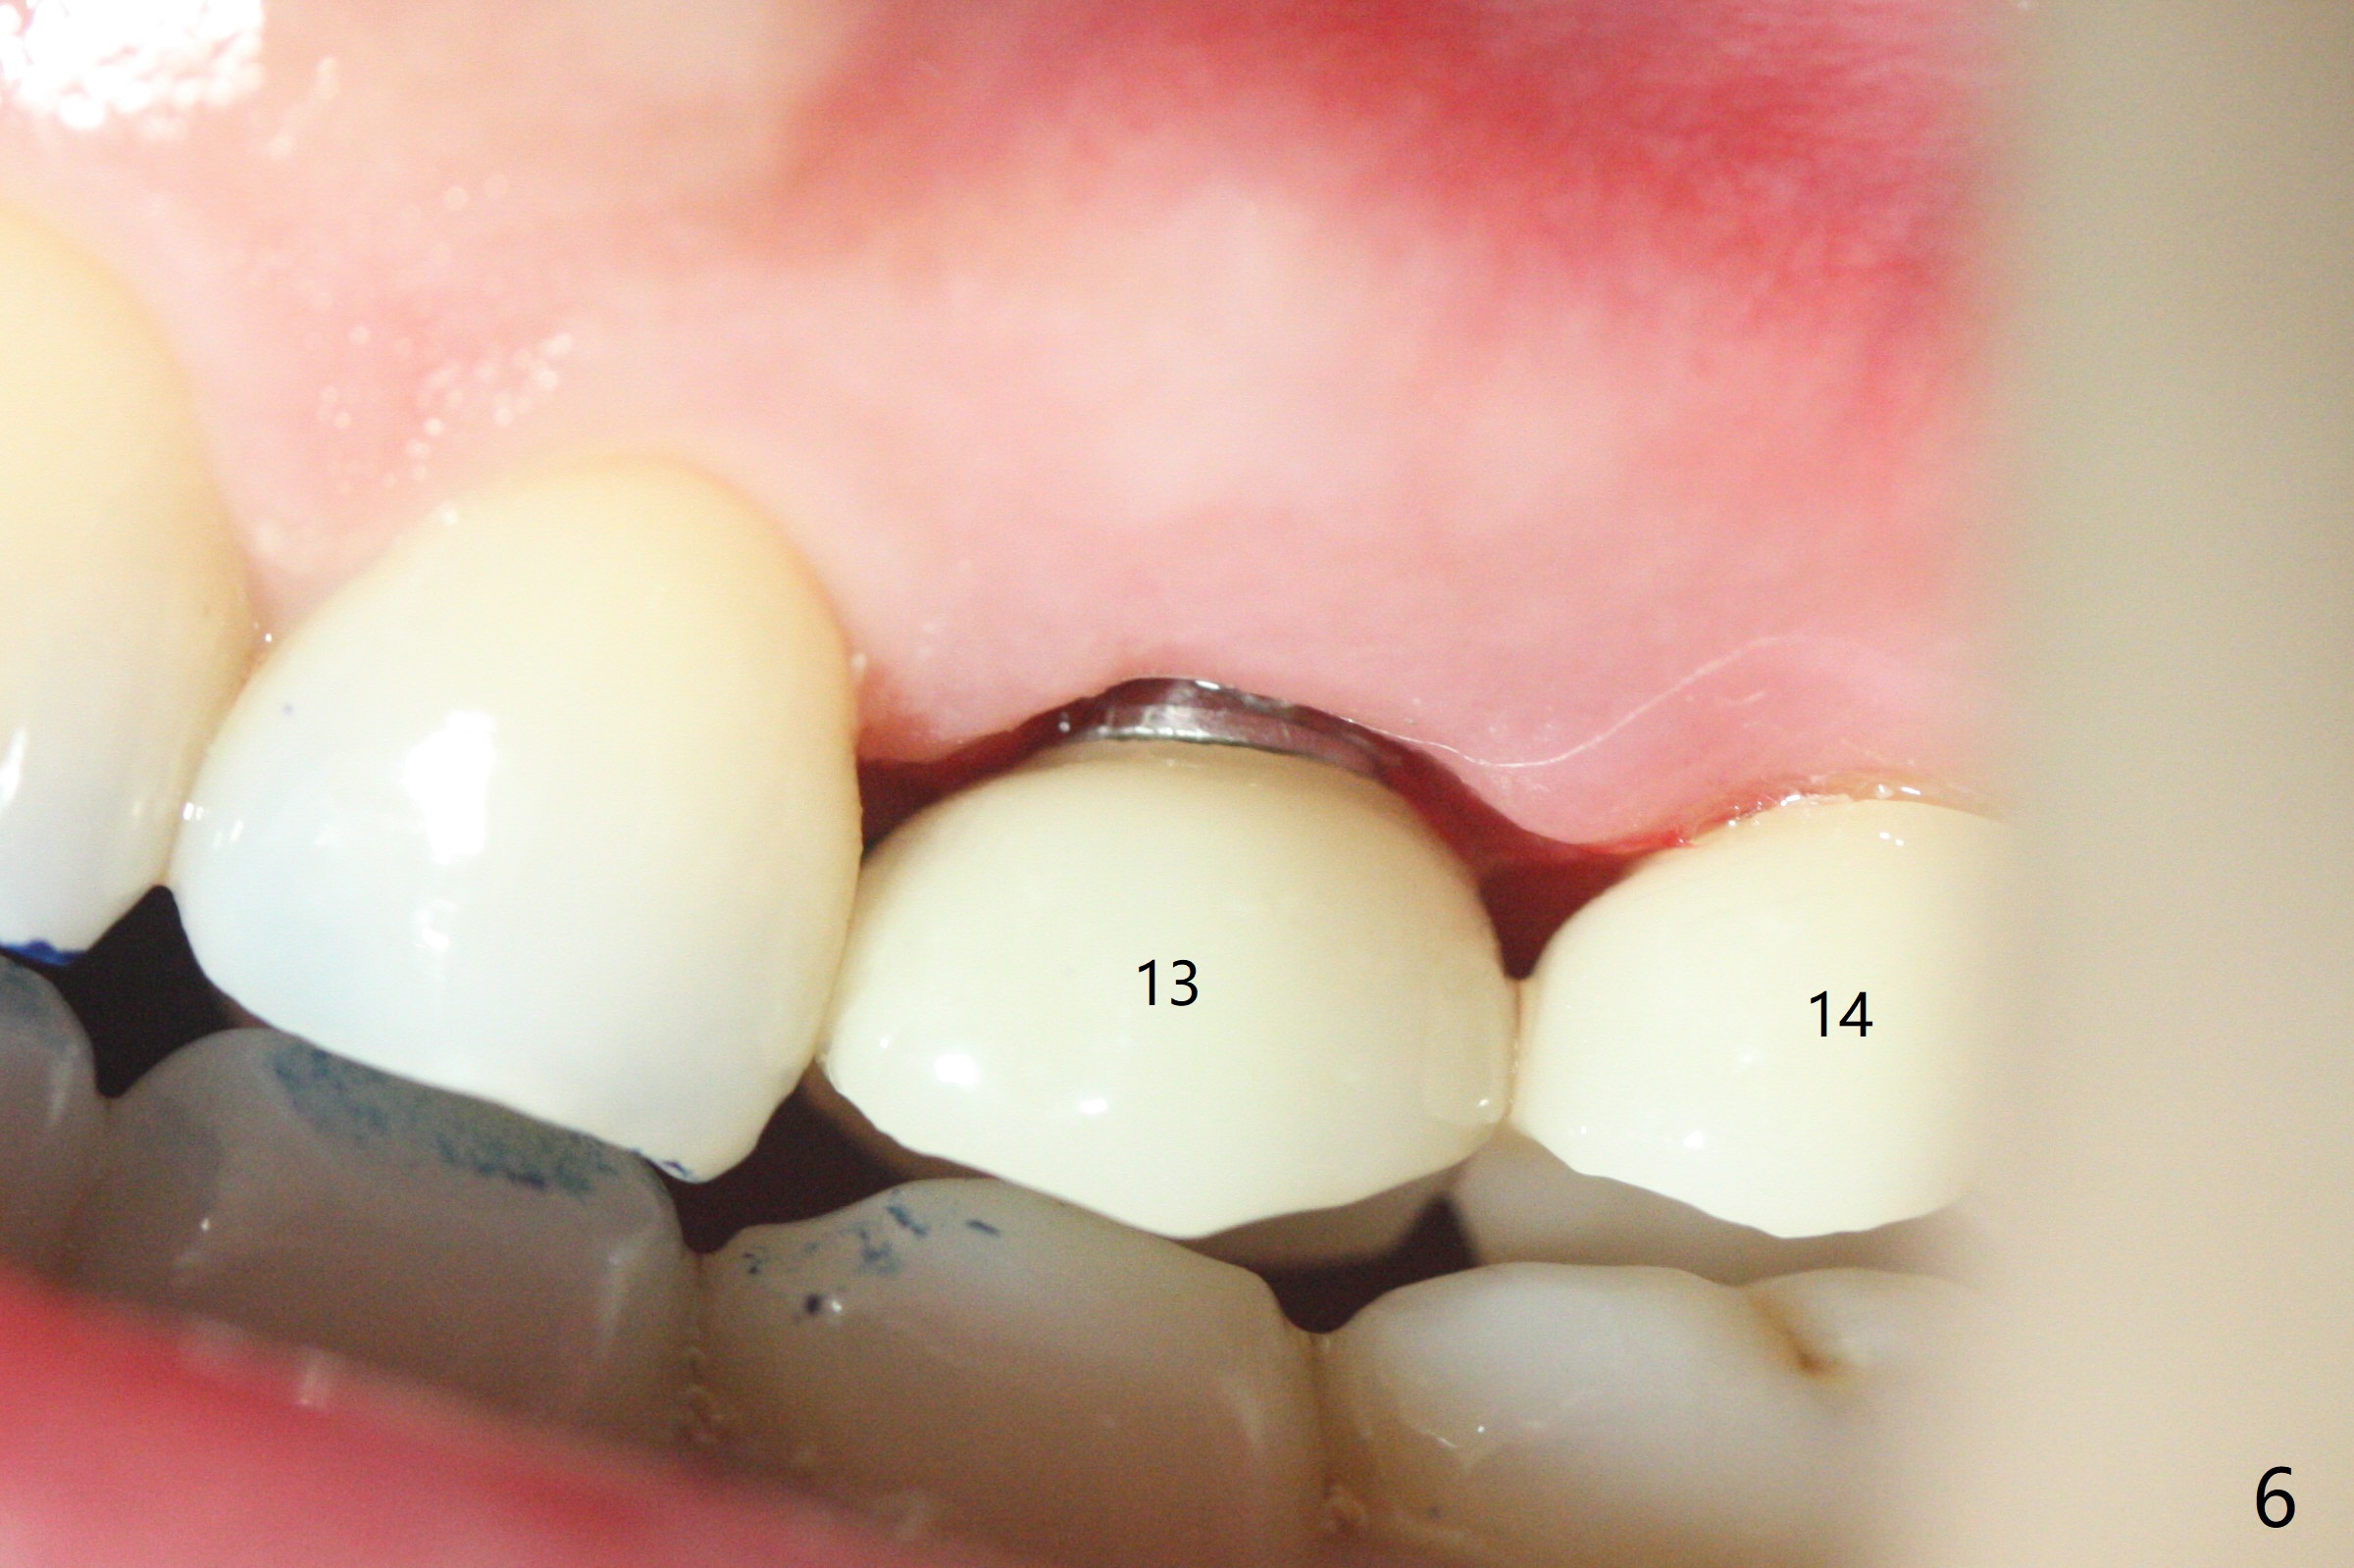

Due to misinterpretation of drill sequence, osteotomy is overprepared in depth (1.5 to 3 mm). When a 4x11 mm dummy implant is placed with > 50 Ncm (Fig.1,2), over placement is ignored. A 4x13 mm final implant is placed with fairly good torque, but it is deeper than expected. When it is backed up, primary stability is lost, in spite of placement of allograft in the osteotomy. Final torque is 15 Ncm. When a 4.5x4(2) mm abutment is placed, the underlying implant turns (Fig.3). A splinted provisional is fabricated at #13 and 14. RCT is retreated 5 months postop (Fig.4 *). An abutment with longer cuff is placed before impression (8.5 months postop, Fig.5). When the crowns of #13 and 14 are delivered, the former looks short and noncosmetic, although the gingiva will grow downward to close the gap (Fig.6). Ideally the gap should be closed with porcelain with overhang (Fig.7).